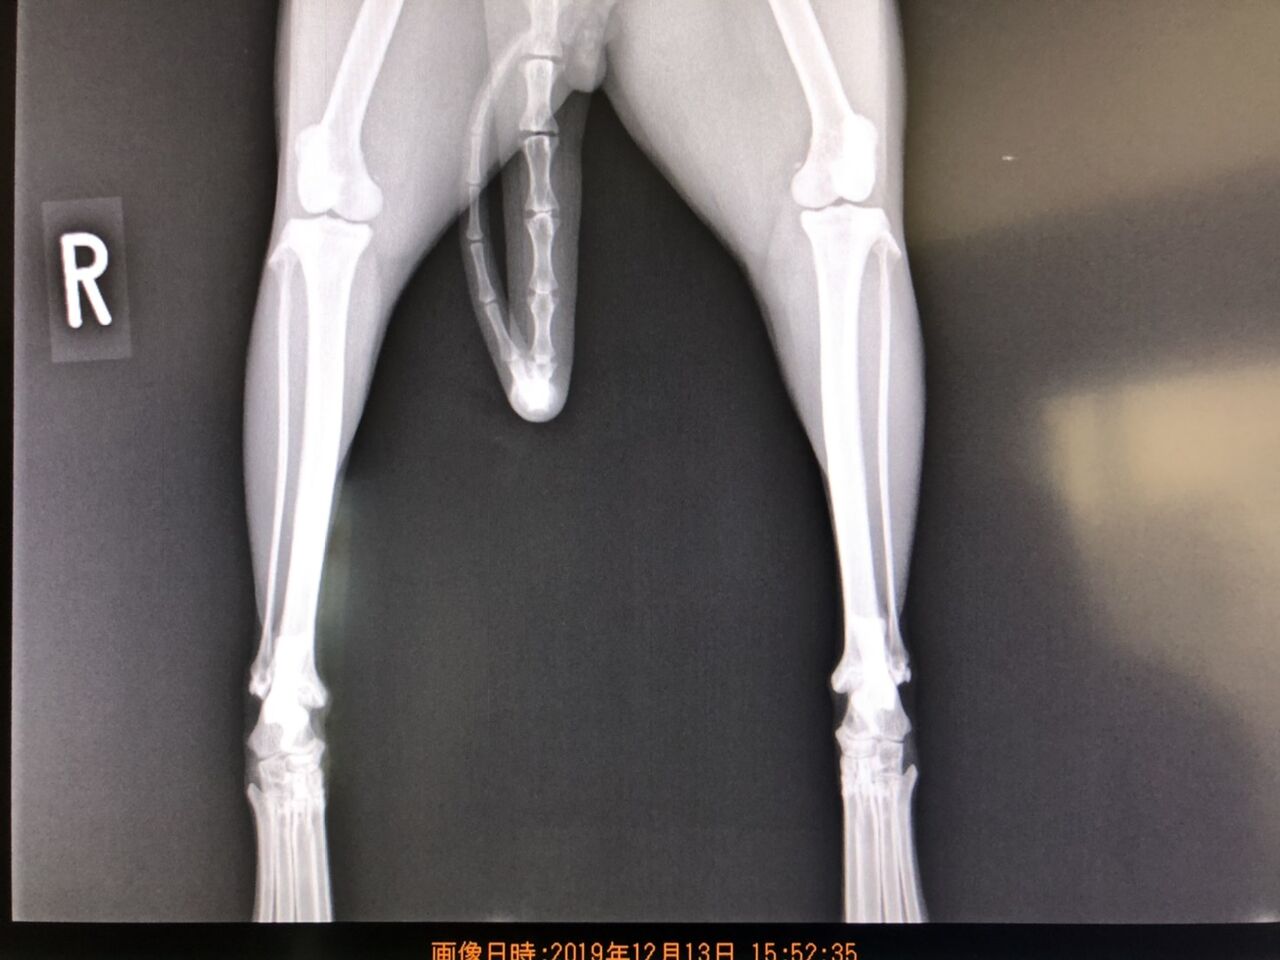

ですが、子猫の保護シーズンの為、次から次へと保護しなければいけない子猫の医療費や(ノミダニ寄生虫の駆除や下痢)怪我した猫などの治療費。